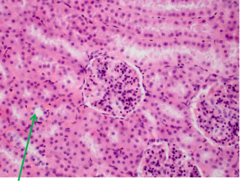

glycogen accumulation vacuoles with indistinct border, nuclei central

Front

Issue? Description?

Back